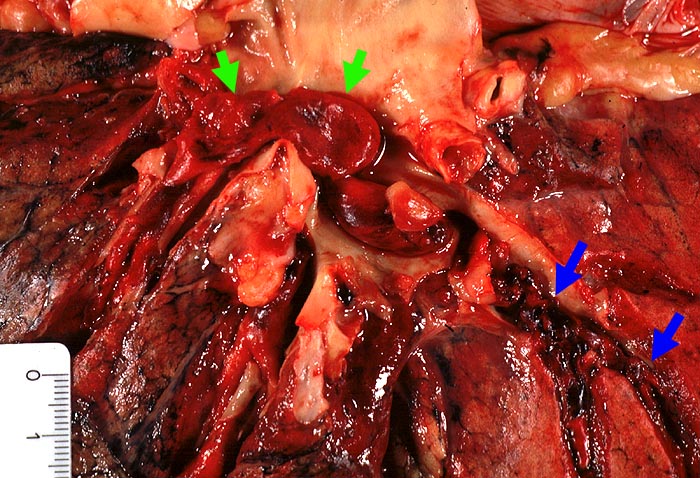

Zentrale Lungenembolie

Im Hauptstamm der Lungenarterie und peripher davon liegende Blutkoagel mit matter Oberfläche.

Nicht ganz frische Beinvenenthrombosen der Unterschenkelvenen beidseits.